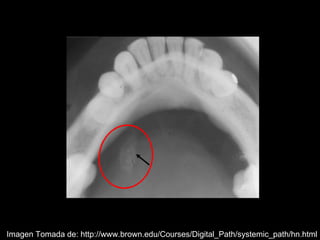

La sialolitiasis es la formación de obstrucciones mineralizadas en las glándulas salivales, causadas por el depósito de calcio y fósforo. Puede presentarse en las glándulas salivales mayores y menores, causando inflamación e hinchazón e incluso dolor durante las comidas. Los sialolitos se ven en radiografías como densidades radiopacas de varias formas y tamaños dentro de los conductos glandulares. El diagnóstico diferencial incluye otras imágenes radiopacas en los tejidos blandos.